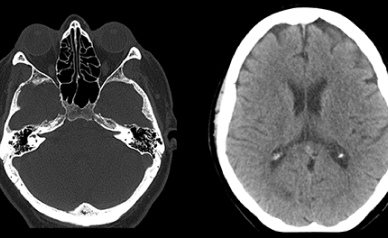

Обследования на новейшем оборудовании Philips Ingenia Ambition 1.5Т и Philips Incisive CT Plus

128 срезов 2022 года, которые обеспечивают максимальную точность, безопасность, удобство и

скорость проведения всех манипуляций.

Снимки высокой четкости

до 1 мм

до 1 мм

- — снимки высокой четкости до 1 мм;